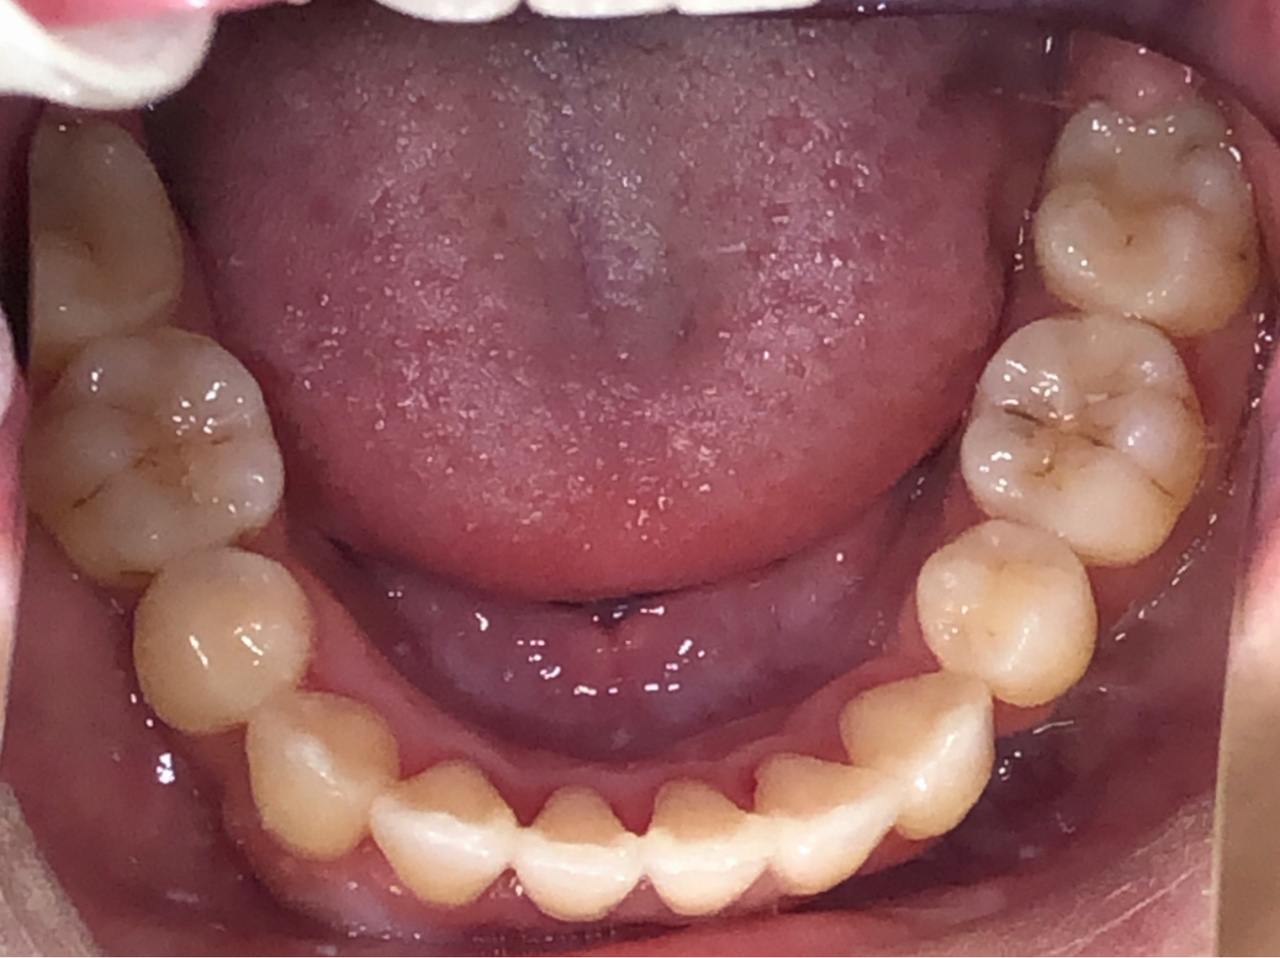

マウスピース矯正の症例

| 主 訴 | 歯のガタつきを治したい |

| 治療詳細 | 歯並びと噛み合わせを整えるため、抜歯とインビアラインを組み合わせた矯正を行いました。まず、歯のスペースを確保するために抜歯を実施。その後マウスピースを使って歯を計画的に動かし、噛み合わせを改善しました。インプラントアンカーを併用しながら、細かい調整を行い、自然でバランスの取れた歯並びに仕上げました。治療後はリテーナーを使用し、安定した歯並びを維持していきます。 |

| 治療期間 | 動的期間 2年11ヵ月 保定期間 1年 4ヵ月 |

| 治療費 | 770,000円 |

| リスク・副作用 | ・歯の動き方には個人差があるため、予想された治療期間より延長する場合があります。 |